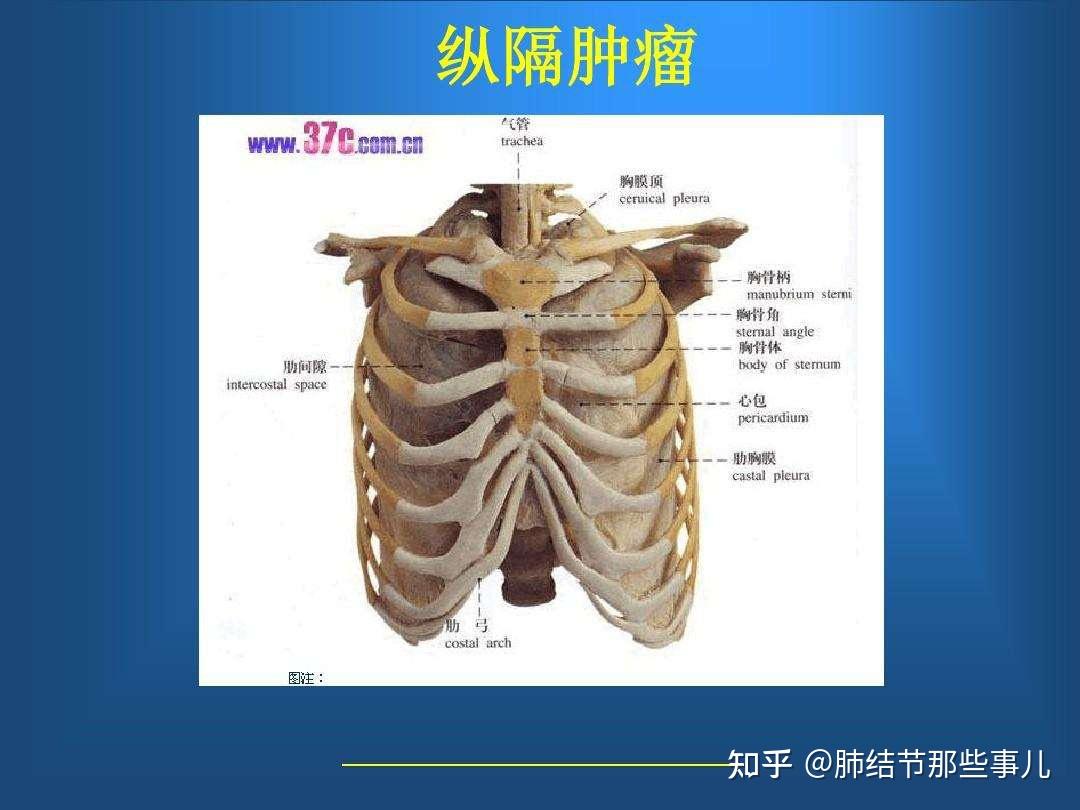

外科学教学课件暨南大学原发性纵隔肿瘤-17号讲课版

图片尺寸920x690